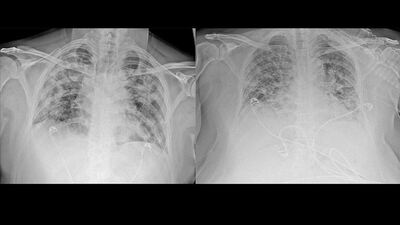

AA, Ankara Şehir Hastanesinde Kovid-19 tedavisi gören hastalara ait akciğer görüntülerine ulaştı. Görüntülerde, hastalığın ne kadar hızlı ilerlediği ve akciğerleri nasıl tuttuğu ortaya çıktı.

Prof. Dr. Karalezli, koronavirüs tedavisi gören hastalara ait akciğer görüntülerinden hastalığın yol açtığı tahribatı ve hastalar üzerindeki etkileri anlattı.

Normal akciğer görüntüleri ile koronavirüs hastalarının akciğer görüntüleri arasında ciddi farklar bulunduğunu belirten Karalezli, şu bilgileri verdi:

"İnsanların aradaki farkları anlamaları için her iki akciğer görüntülerine de yer verdim. Görüntülerdeki beyazlıklar akciğerdeki tutulumu gösteren görüntüler ne yazık ki. Bu hastalar yoğun bakım hastaları. Filmler birbirine az çok benzeyen şekilde. Altta yatan hastalığı olanlarda ise daha kötü seyrediyor."

Kliniğe yeni başvuran bir hastanın, 5 Ağustos'ta çekilen tomografi görüntülerindeki tipik koronavirüs görüntülerinin olduğunu ifade eden Karalezli, hastanın bir hafta içerisindeki tomografi görüntüsünde ciddi değişiklik olduğunu ve enfeksiyonun çok arttığını söyledi.